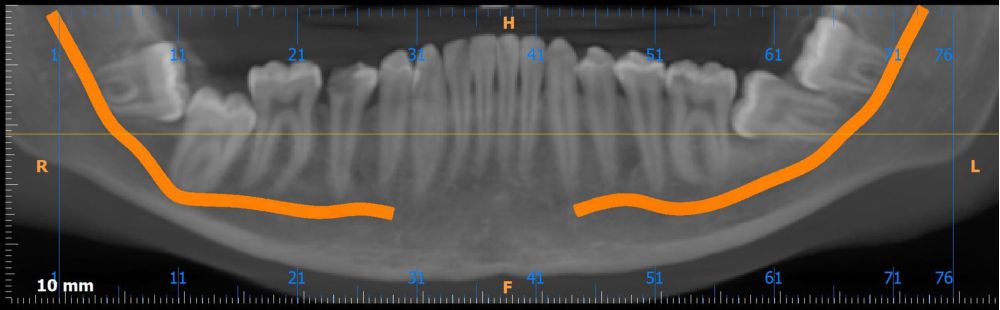

Métodos: Se presenta el caso clínico de un paciente varón de 18 años en el que, tras la realización de una CBCT de la arcada mandibular, se observó la retención de los segundos molares mandibulares permanentes junto con los terceros molares mandibulares.

Conclusiones: La retención del segundo molar mandibular es un hallazgo creciente en jóvenes y requiere un diagnóstico precoz para evitar complicaciones, siendo la CBCT la herramienta diagnóstica más precisa para evaluar la posición y riesgos asociados. Las opciones terapéuticas son diversas y siempre deben individualizarse según la anatomía, el pronóstico y las características del paciente.

Methods: We present the case of an 18-year-old male patient in whom, after performing a CBCT of the mandibular arch, retention of the permanent mandibular second molars was observed, along with the mandibular third molars.

Conclusions: Retention of the mandibular second molar is becoming more common in young patients and needs to be diagnosed early to avoid complications. CBCT is the most accurate tool to assess the tooth position and possible risks. Treatment options vary, and they should always be based on the patient’s anatomy, prognosis, and individual characteristics.